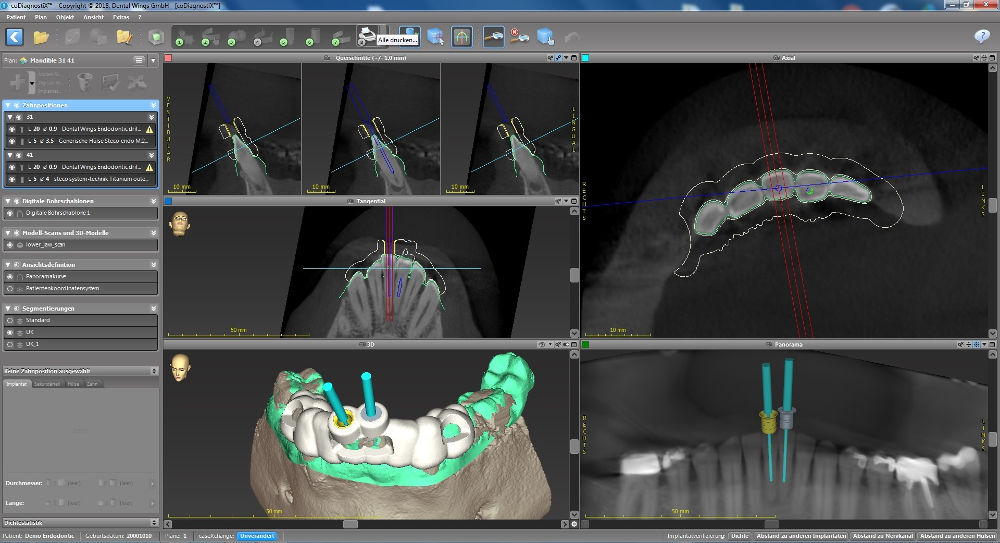

Bohrachse am Computer definieren, Planungssoftware coDiagnostiX™

Auf Basis dreidimensionaler Röntgenverfahren, lassen sich die Strukturen obliterierter Zähne virtuell darstellen.

Hierbei verwenden wir die Planungssoftware coDiagnostiX™, die sich bereits in der Implantatplanung bewährt hat. Üblichweise dienen DICOM

Daten als Basis für die softwarebasierte Planung. Der Zugang zur Kavität kann in der Software präzise geplant und die

Bohrachse entsprechend ausgerichtet werden. Sinnvoll ist hierbei auch die Darstellung der Bohrergeometrie.

Endodontie durch die Bohrschablone, coDiagnostiX™

Eine auf den Bohrer abgestimmte Bohrhülse wird in die geplante Bohrschablone eingefügt, so dass auch eine

Tiefenkontrolle möglich ist. Die Geometrie der Bohrschablone wird exportiert und kann entweder gefräst oder gedruckt

werden. In die Bohrschablone wird die Bohrhülse aus Titan eingesetzt und führt den Bohrer entlang der zuvor bestimmten

Achse, so dass der Kanal wie geplant aufbereitet werden kann.